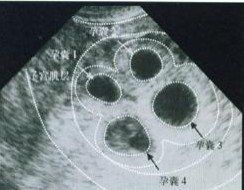

形成雙卵雙胎原因是由兩個卵子同時受精後形成兩個受精卵,並分別植入子宮壁的蛻膜層內,各自發育成長為雙胞胎。這種雙胞胎是兩個胎兒各有單獨的胎盤、絨毛膜和羊毛膜,兩個胎盤之間的血液循環並不相通,兩個胎兒安居在各自的胎囊里,兩個胎羊膜之間有兩側羊膜和兩層絨毛膜所組成的中隔。 (一般相貌非常相近的雙胞胎是“單卵雙胎”)

雙胞胎親們都希望是龍鳳胎,而雙卵雙胎這樣的情況才有可能出現龍鳳胎。雙卵雙胎中只有25%的幾率成為龍鳳胎;雙卵雙胎的胎兒,性別、血型可以相同也可以不同,面貌與一般親兄弟姐妹一樣。單卵雙胎的特點是兩個胎兒的血液循環通過胎盤互相通聯。因此單卵雙胎的胎兒,血型及性別完全相同,面貌也很難辨認。生雙胞胎跟基因,人種,藥物等都有關係。世界上生雙胞胎幾率最高的國家是千分之十五,而我國的幾率是千分之五左右,生龍鳳胎的機率則更是小得多。